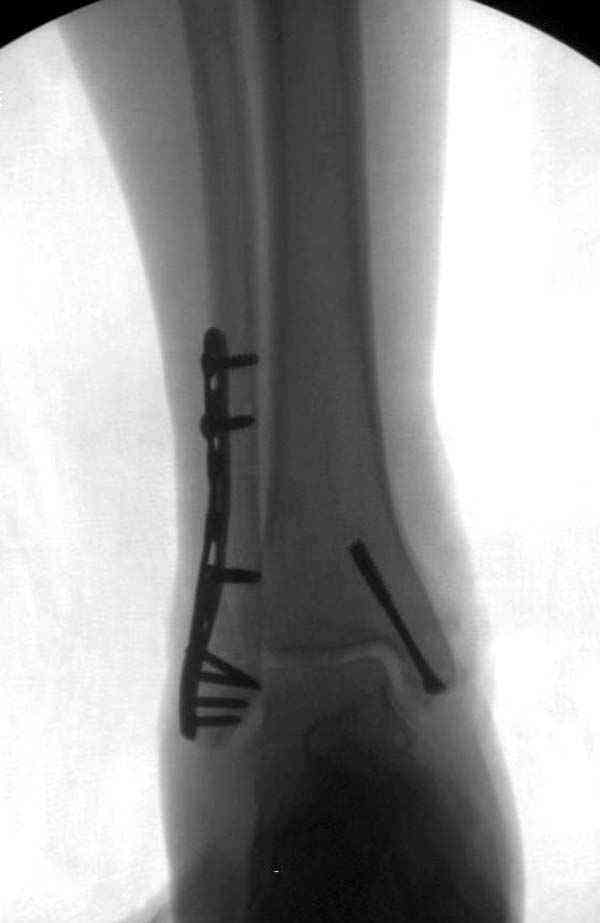

Нет первичных снимков, перелом очень низкий и под большим сомнением диагноз разрыва синдесмоза. Медиальная сторона отрепонирована на "хорошо" и, по-видимому, прорезание проволоки произошло во время операции. Без снимков трудно судить о высоте малоберцовой, а лодыжка находится в варусе. Лагирование получилось, но возле тонких шурупов передне-задний шуруп выглядит немного тяжеловато.

Во всех руководствах АО имеется описание техники применения низкопрофильных пластин 1/3 трубки, которые могут быть применены для фиксации наружной лодыжки. Фиксацию проводят кортикальными 3.5 мм шурупами, и если дистальная фиксация недостаточная, тогда усиливают конструкцию созданием hook plate. Сгибая конец пластины на последнем отверстии, внедряют его в дистальный отдел, и тем самым создается дополнительная фиксация.

Здесь несколько частных случаев: перелом голеностопа со сравнительными снимками и разрыв синдесмоза, а также медиальная Hook пластина.